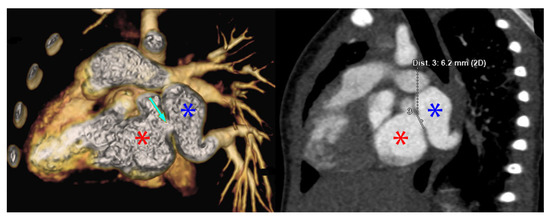

Using PVS as an initial search term, 57 cases from 24 different institutions were identified and included for analysis. Table 1 is a list of the institutions reporting cases of PVS and Figure 1 is a map of this. Figure 2 and Figure 3 are of a computed tomographic (CT) scans performed on described cases from Malaysia (Figure 2) showing repaired TAPVR with recurrent stenosis and Vietnam (Figure 3) showing idiopathic common left pulmonary vein stenosis.

Figure 2.

CT scans from the above described patient from Malaysia with repaired supracardiac TAPVR with recurrent PVS. The image on the left is a 3D reconstruction of a CT angiogram. The blue star denotes the pulmonary vein confluence, the red start denotes the left atrium. The light blue arrow on the left image denotes the area of stenosis. The image on the right that of the traditional CT angiogram with blue and red stars denoting the pulmonary veins and left atrium, respectively. The line measures the stenosis at 6.2 mm. Cross sectional imaging such as this allows institutions to risk stratify cases and offer surgery to those patients with the best predicted outcome.

“The patient was a 1 month old, ex-33 week gestation, child with failure to thrive. She was diagnosed with supracardiac TAPVR which was obstructed at the entry into the vertical vein. She underwent urgent repair of at 1 month of age at another tertiary care hospital. 3 months following surgery, an echocardiogram revealed mild to moderate pulmonary vein stenosis at the pulmonary anastomotic site for which she was transferred to the National Heart Institute. A CT revealed all pulmonary veins draining into the left atrium with severe stenosis at the pulmonary vein confluence to left atrium anastomosis. A re-operation was performed to relieve the pulmonary vein stenosis 9 months following the initial surgery using the sutureless technique. On discharge the echocardiogram showed a wide open pulmonary venous confluence with no gradient across the anastomotic site (Figure 2).”—Sivakumar Sivalingam, FRCS(C.Th), Clinical Director Congenital Heart Surgery, Kuala Lumpur, Malaysia